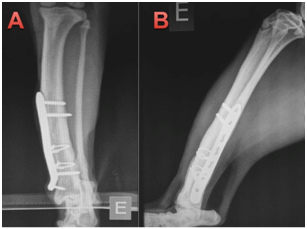

Animals were weight bearing at the time of suture removal by 10days the postoperative. On the same day, the limb was examined for weight bearing, palpation at the surgery site, absence of crepitation and instability. At 21days no callus was observed on control radiographs and the implants showed no signs of loosening in both cats. Further radiographs were taken at 42 and 63days, after which time patients were clinically discharged. One of the animals had a four month follow up in the postoperative period and secondary callus was not present in cat 1 or 2, in Figures 5 and 6, respectively. No clinical or orthopedic changes were found after 4months postoperatively (Figure 5) (Figure 6). Some previous studies have postulated that the high incidence of non-union in feline distal tibial fractures is related to a combination of unstable fixation, inadequate blood supply, excessive fracture gaps and interposition of soft tissue between fracture fragments.1 Compression of the fracture line provides continuous bone contact and thus minimizes strain, permitting primary healing.10‒15 Restoration of the bone column by compression of the fracture line also results in rigid stability allowing the weight load to be shared between the bones and implant,10‒13 and decreasing the chances of implant loosening.12

Figure 5 4 months postoperative of the cat 1. In all the images the bone consolidation in tibia has occurred without the production of primary bone callus, showing the total fragmentary compression caused by the cerclage.

1. Mid-lateral radiograph with cerclage wires and blocked plate with neutral function.

2. Close up showing primary bone callus.

3. Craiocaudal projection, showing cerclage.

Figure 6 4 months postoperative of the cat 1. In all the images the bone consolidation in tibia is seen without the production of primary bone callus, showing the total fragmentary compression caused by the cerclage.

1. Crabiocaudal projection showing bone cerclage (compression) and blocked plate with support function. Primary tibial callus is observed in tibia and secondary in tibia.

2. Medio-cranial projection with the same implants as A, showing primary bone callus.